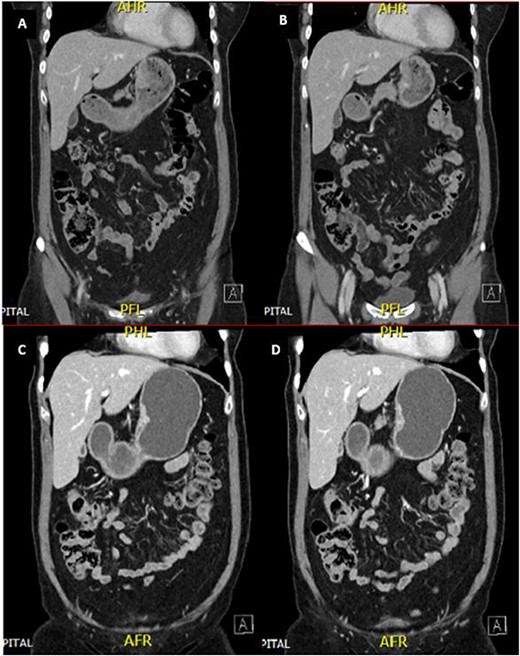

A 65-year-old female was referred to the general surgical outpatient clinic with a 6-month history of epigastric pain and dyspepsia. The patient’s only other medical history was eczema. Physical examination revealed a soft abdomen with no palpable mass. A 10 cm fungating, malignant appearing mass was identified along the gastric lesser curvature on upper gastrointestinal endoscopy (Fig. 1). Histopathology of the biopsied mass demonstrated spindled and small round blue cell tumor with immunohistochemistry staining consistent with Ewing-like sarcoma. Computed tomography (CT) of the abdomen and pelvis showed an enhancing nodular lesion with central calcification and an indeterminate 4 mm lymph node along the lesser curvature of the stomach which raised concerns for gastric malignancy (Fig. 2). Intense fluorodeoxyglucose (FDG) uptake was noted along the lesser curvature of the stomach on staging positron emission tomography (PET) (Fig. 3). There was no evidence of distant metastasis.

CT abdomen and pelvis demonstrated an enhancing nodular lesion along the gastric lesser curvature (A and B). Interval CT abdomen and pelvis showed reduced gastric wall thickening following 7 weeks of chemotherapy (C and D).

The patient was planned for a 12-week neoadjuvant chemotherapy following discussion with the sarcoma unit and upper gastrointestinal multidisciplinary meeting but her treatment was ceased on the 7th week due to side effects from her chemotherapy regime (Doxorubicin, Vincristine, Cyclophosphamide, Etoposide, Ifosfamide). Interval CT of the abdomen and PET imaging showed reduced FDG uptake at the gastric lesser curvature and reduced gastric wall thickening (Figs 2 and 3).